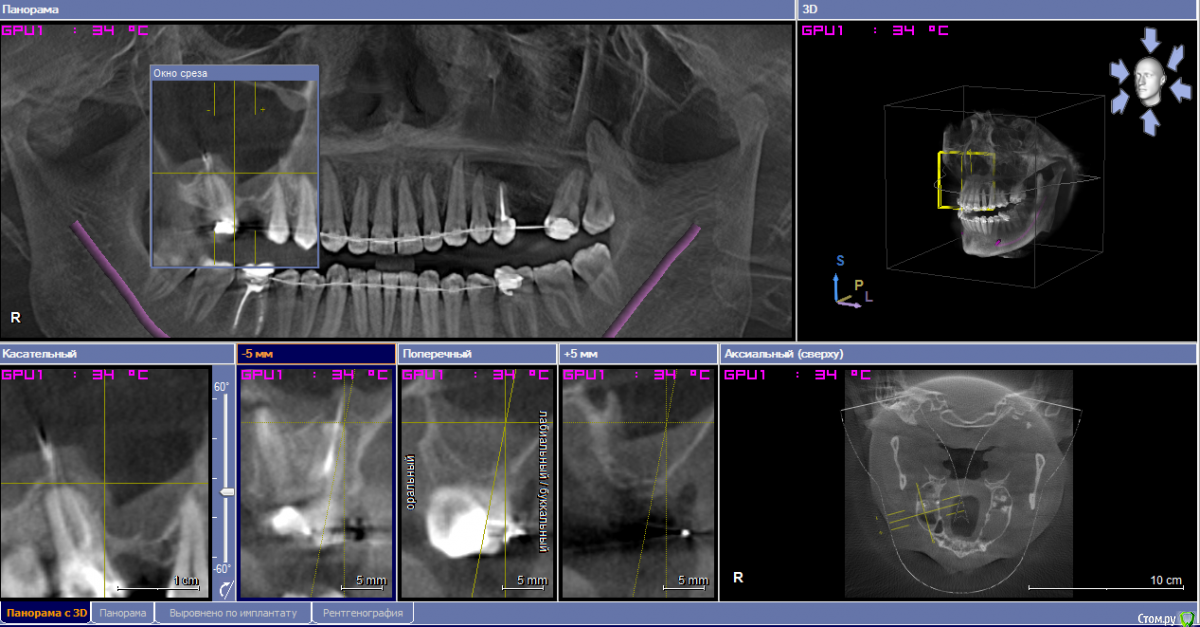

___49___ Опубликовано 15 февраля, 2019 Поделиться Опубликовано 15 февраля, 2019 Уважаемые коллеги , прошу совета, или просто мыслей в слух - как поступить в данной клинической ситуации ? фото прикладываю ниже , хотелось бы выполнить открытый синус слева с одновременным удалением кисты - как это правильнее воплотить технически , обязательна ли гистология , какие "подводные" камни могут быть , какие материалы лучше иметь под рукой ? Справа пока не определился - может ретроградку сделаю через окно с открытым синусом одновременно может удалю ..не суть - пока вопрос по левой стороне . спасибо . Ссылка на комментарий

pit Опубликовано 16 февраля, 2019 Поделиться Опубликовано 16 февраля, 2019 Уважаемые коллеги , прошу совета, или просто мыслей в слух - как поступить в данной клинической ситуации ? фото прикладываю ниже , хотелось бы выполнить открытый синус слева с одновременным удалением кисты - как это правильнее воплотить технически , обязательна ли гистология , какие "подводные" камни могут быть , какие материалы лучше иметь под рукой ? Справа пока не определился - может ретроградку сделаю через окно с открытым синусом одновременно может удалю ..не суть - пока вопрос по левой стороне . спасибо .Можно отпунктировать и поднять, это самый простой вариант. Или удалить через разрез слизистой, ретенционная киста легко отделяется от слизистой. Но с юридической точки зрения правильнее направить к ЛОР на эндоскопию и через 2 мес выполнить ОСЛ. 6 Ссылка на комментарий

Nazim_NV86 Опубликовано 16 февраля, 2019 Поделиться Опубликовано 16 февраля, 2019 (изменено) Если такого лора нет поблизости, то удалить через разрез слизистой, ретенционная киста легко отделяется от слизистой.Мне приходится именно так и делать. Судя по всему соустье там рабочее. Поэтому дополнительное окно над 25 позволит убрать оболочку. Алгоритм такой:1. Делаем окно над 25 и иглой откачиваем содержимое. 2. Делаем окно над 26 и отслаиваем3. Надрез слизистой над 25 и извлечение оболочки4. Мембрана, графт, имплант и т.д.Если есть ещё варианты, всегда готов к новым методам. с юридической точки зрения правильнее направить к ЛОР на эндоскопию и через 2 мес выполнить ОСЛ. Всегда об этом думаю. Даже в процессе операции Изменено 16 февраля, 2019 пользователем Nazim_NV86 2 Ссылка на комментарий